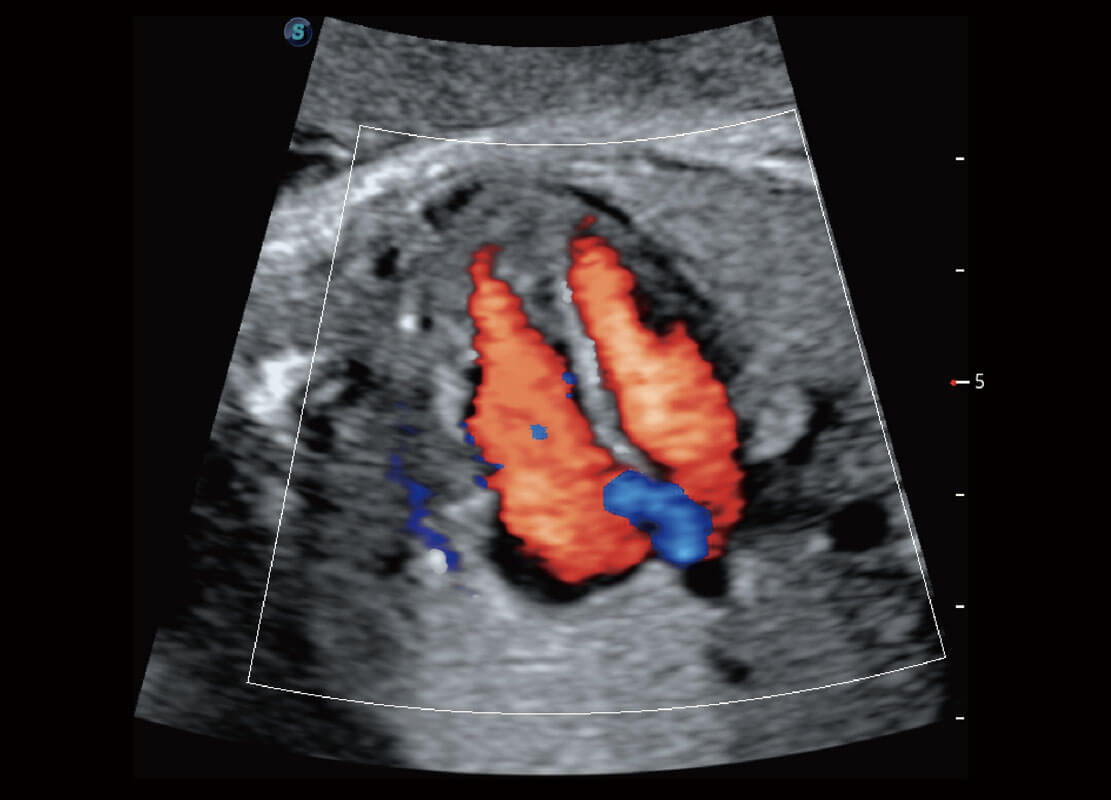

P60优异的图像质量搭载专科探头,在妇科基础疾病的诊断、卵泡生长的监测、输卵管通畅情况的判别等方面为您提供生殖应用方案。

腔内妇科-宫腔分离

腔内妇科-卵巢

腔内三维-宫内节育器

腔内三维-光影成像